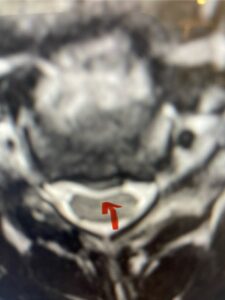

In this next case, this patient is a 47 year-old female who presents with intractable low back pain with severe pain, numbness, and weakness in the right lower extremity that had gotten progressively worse over a year. The patient had failed conservative management including physical therapy and epidurals. She was noted to have ⅘ weakness of plantar flexion. MRI demonstrated a large right L5-S1 disc herniation with severe compression of the descending right S1 nerve root (Fig 3). It was decided to perform a right L5-S1 hemilaminectomy for removal of the disc fragment and decompress the S1 nerve root. When you expose the disc, one must be certain to release any anterior adhesions to the nerve root in order to prevent a dural tear during retraction of the nerve root. It is also important to make sure during exposure and you finally encounter the dura after removing the ligamentum and fat, to make sure you are looking at the nerve root and not the main trunk of the thecal sac because if you don’t you can avulse or damage the nerve root if you retract the wrong structure.

Fig. 3a: Sagittal and axial T2-weighted lumbar MRI images demonstrating large right L5-S1 disc herniation (red arrows)

Fig. 3b

We found a massive subligamentous herniation which had to be revealed by having your partner retract the freed nerve root with a nerve root retractor and putting slight downward pressure on the more medial and anterior disc space. There is nothing more satisfying when the jelly (disc fragment) of the annulus (donut) comes squirting out and you remove a large chunk of disc material that clearly was stretching the ligament membrane and compressing the nerve root. This does cause back pain in addition to radiculopathy not only by the component of mechanical compression but also the stretching of the nerves within the ligament. We performed this surgery and noted that the nerve root was a very angry red color or hyperemic and we removed a large subligamentous fragment. The patient had improvement of her preoperative radicular symptoms.